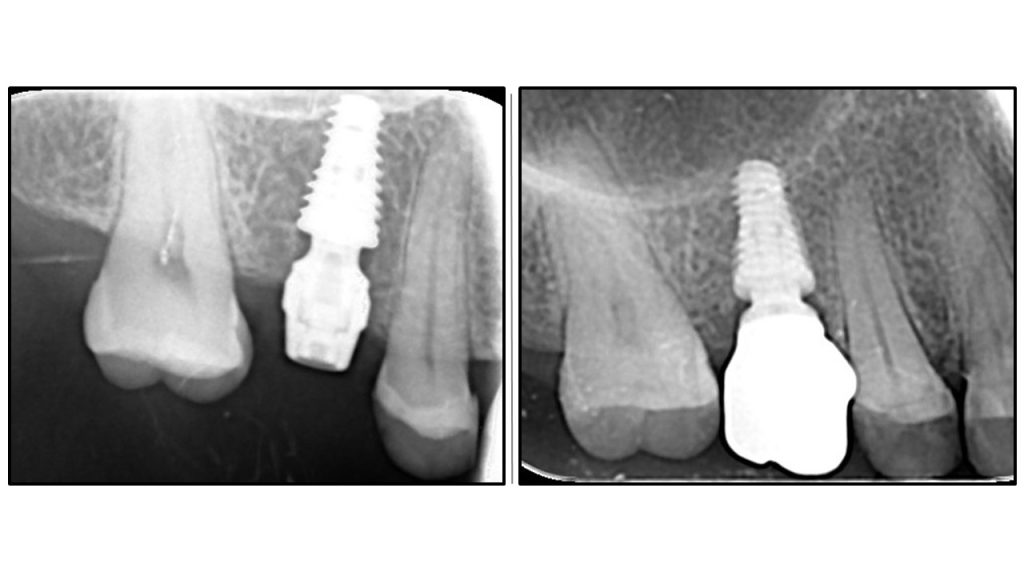

Another example of One Abutment One Time protocol

Bicortical stability achieved by the abutment.

Bicortical stability by apical engagement of the compact sinus floor and crestal bone by an abutment

immediate implant placement with oaot

Immediate placement with one abutment one time still yields the same results